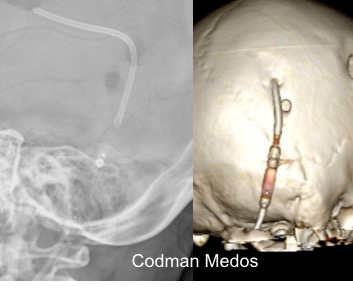

il existe un grand nombre de valves ; il n’est pas toujours aisé de les reconnaitre radiologiquement. voici la liste des plus courantes :

comment reconnaitre radiologiquement le type de valve ?